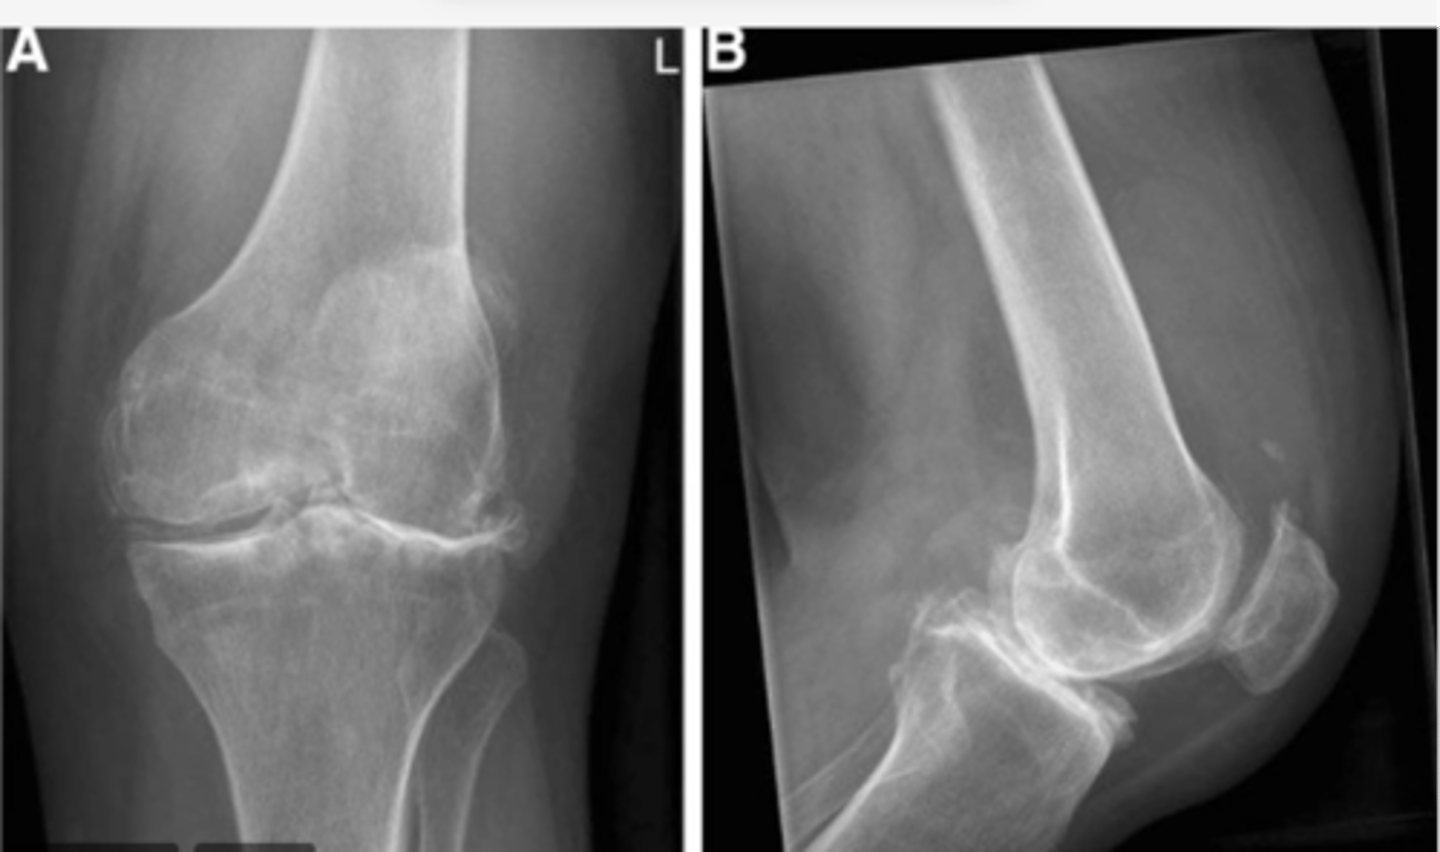

View: AP

Structure: left shoulder

State the type of view and structure being depicted.

View: right lateral

Structure: right knee

Femur shifted MEDIALLY over tibia; patella shifted SUPRALATERALLY; bone spur on the lateral tibial plateau

Work through your "ABCS". Start with A: alignment.

Sclerosis along bilateral tibial plateaus -- more pronounced laterally (hallmark of OA, along with the bone spur noted in "A: alignment")

Work through your "ABCS". Start with B: bone density.

Loss of joint space along the lateral tibiofemoral component. Diminished joint space along the medial side.

Work through your "ABCS". Start with C: cartilage space.

Calcification superior to the patella, Baker's cyst on the posterior side, LOTS OF SWELLING

Work through your "ABCS". Start with S: soft tissue.